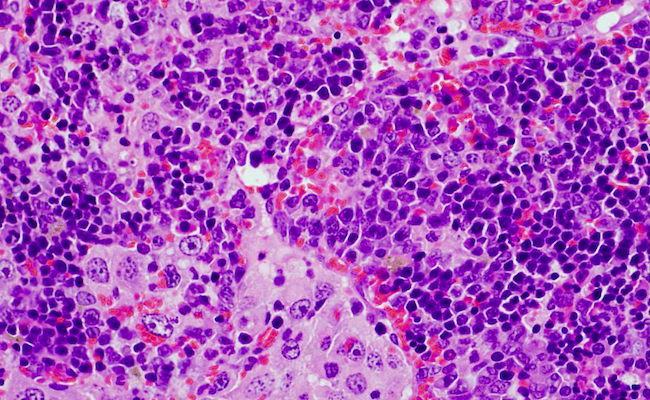

Una alteración genética que afecta al gen VAV1 desempeña un importante papel en tumores derivados de los linfocitos T (linfomas) y el cáncer de pulmón, dos tipos de cánceres que se caracterizan por tener tasas de supervivencia muy bajas. Esta es la principal conclusión de un estudio liderado por el Consejo Superior de Investigaciones Científicas (CSIC).

“Por un lado, hemos demostrado que la alteración genética en VAV1 no es suficiente para inducir la formación de tumores en ningún órgano de los ratones. Sin embargo, cuando se combina con la eliminación del gen antitumoral TRP53 provoca el rápido desarrollo de un tumor muy específico de linfocitos T conocido con el nombre de linfoma periférico de células T. Pero no se han detectado otros tipos tumorales, indicando que la combinación de estas dos alteraciones genéticas solo da lugar a un tipo de tumor”, señala Robles-Valero.